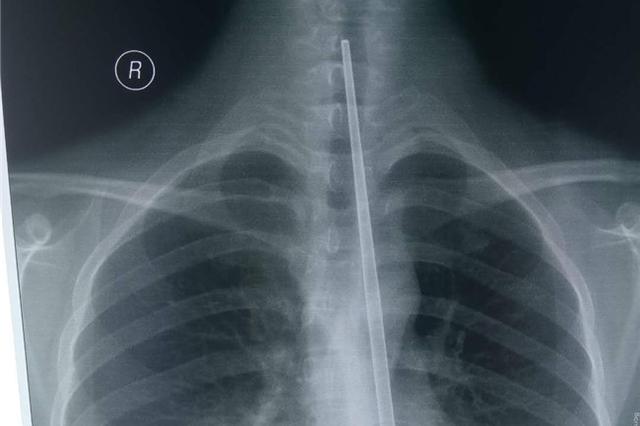

扬子晚报网7月22日讯(采访人员 张凌飞 通讯员 孙利 张琳)胃部不适,想用筷子自行催吐,不料27厘米长不锈钢筷子经口腔滑入食道。7月21日,连云港患者张女士紧急到连云港市第二人民医院就医。医生买同材质长筷加班加点,多次模拟手术,最终耗时十分钟,用胃镜取出这一异物。

当日午饭后,连云港市市民张女士感觉胃部不适,想用筷子刺激喉咙以催吐,不慎将不锈钢筷子滑进食道。当天下午3时左右,她在家人陪同下,到连云港市第二人民医院就医求助。

耳鼻喉科副主任医师何志龙接诊。在确定筷子的位置后,何志龙尝试喉镜下取筷,但筷子又重又滑,且较深,没有成功。